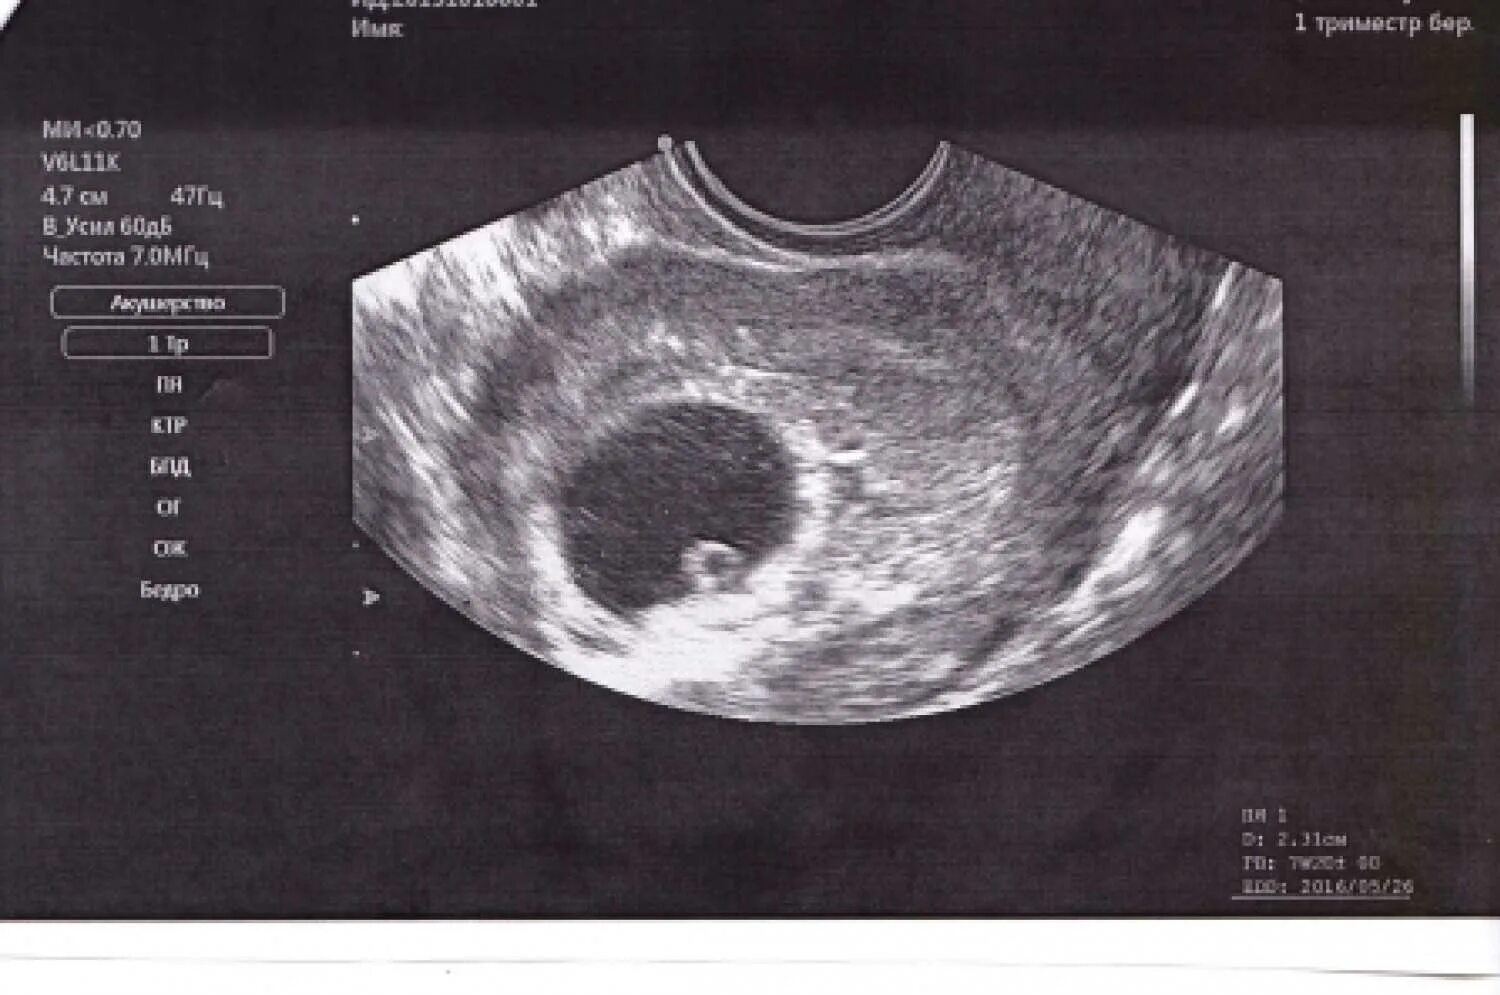

Увидят ли на 4 неделе беременность